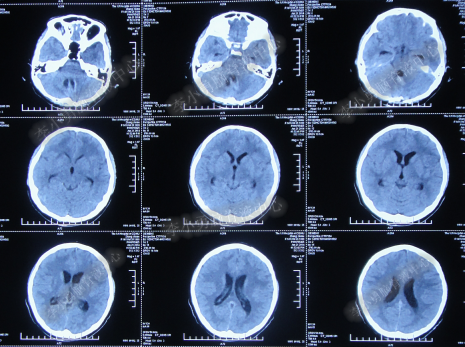

腰大池持续引流20天内,体温仍间断高热,曾3次脑脊液细菌培养均示鲍曼不动杆菌,先后使用利奈唑胺+克倍宁,利奈唑胺+克倍宁+奥硝唑,舒普深+米诺环素+来立信+氟康唑,舒普深+米诺环素+美罗培南+氟康唑,及日达仙、人免疫球蛋白提高免疫力,但颅内感染仍控制不住,期间多次头部CT检查均示脑室无明显扩张(图-7、图-8、图-9)。

图-7:2014年6月9日头部CT

图-8:2014年6月14日头部CT

图-9:2014年6月21日头部CT